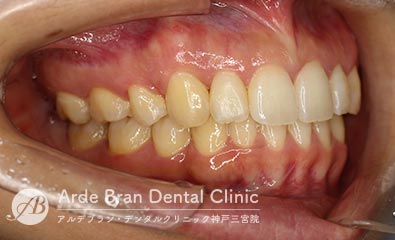

- 上顎前突(出っ歯)/叢生

(20代女性 治療期間2年5カ月) - 前歯の突出感と歯のがたつきを改善したいとの事でご来院されました。なるべく目立たない装置で治療をしたいとご希望されたのでマウスピース矯正にて治療を行いました。治療途中に治療計画とのズレが生じましたが、顎間ゴムを使用しリカバリーを行いワイヤーで修正をかける事なくフィニッシュ出来ました。ワイヤーを併用だともう少し治療期間は短縮出来たかと思います。口元の突出感が改善し、歯磨きもしやすくなったとお喜び頂きました。

- 治療前

- 治療後

| 装置名 | インビザライン (マウスピース矯正) |

|---|---|

| 抜歯非抜歯 | 上顎第一小臼歯の抜歯(合計4本) |

| 治療期間 | 2年5カ月 |

| 費用 | インビザラインフル(難症例) 79万円+TAX 抜歯(5千円+TAX)×4本 再印象(5千円+TAX)×2回 顎間ゴム500円×数個 |

| リスク副作用 | 装置装着による違和感、歯の移動時の痛み、歯根吸収など。詳しくはこちらをご参照ください。 |